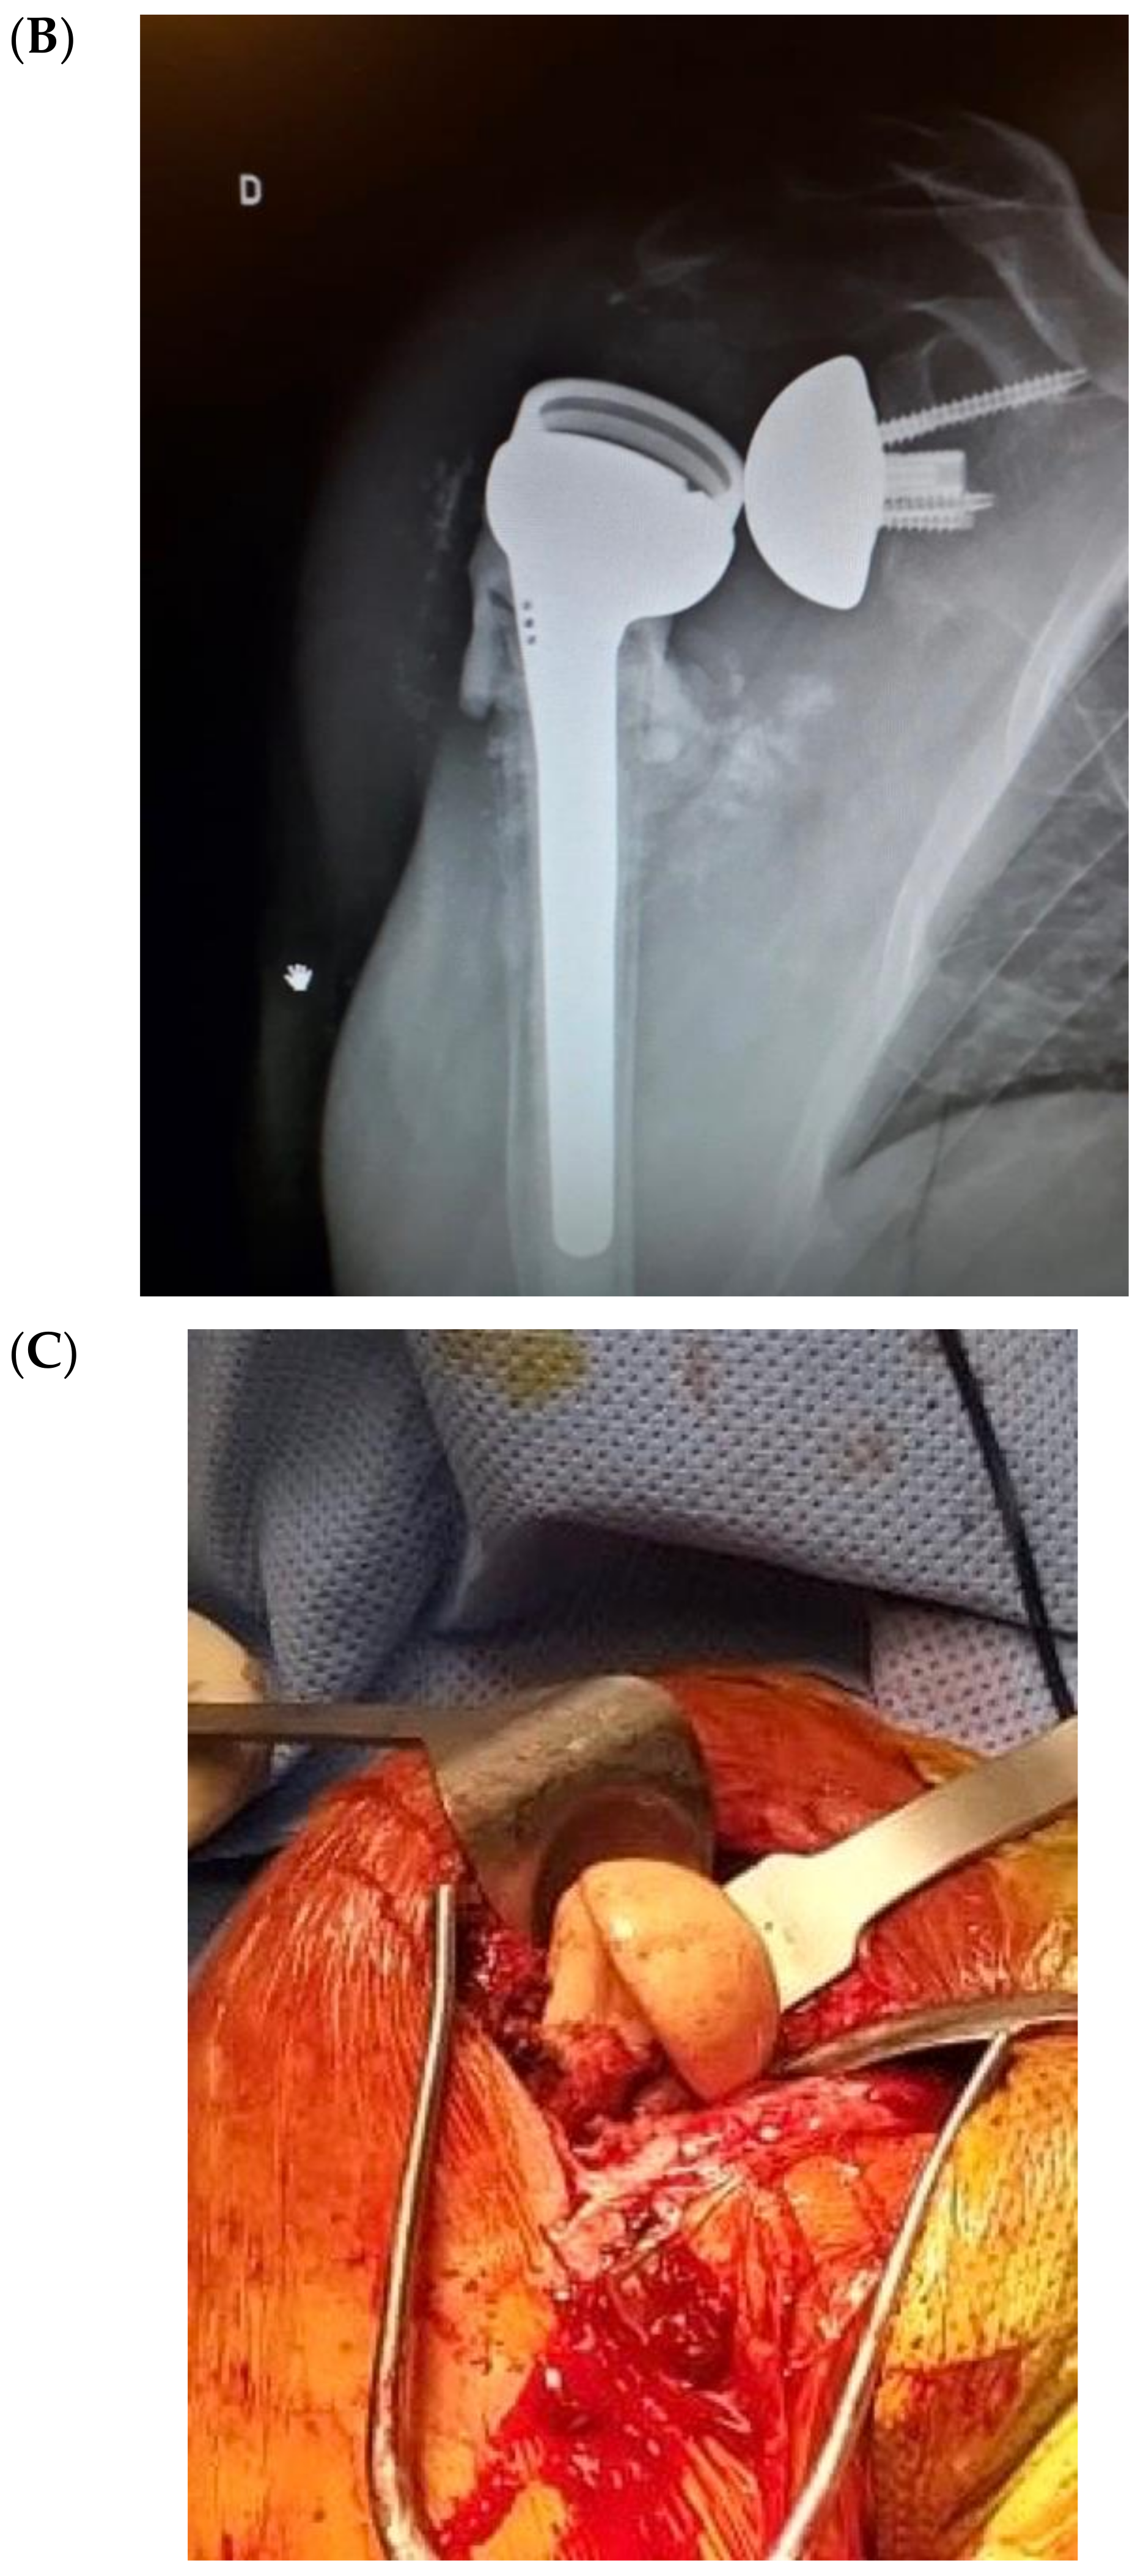

A porous tantalum cone (Zimmer, Warsaw, IN, USA) was employed for extensive defects of humeral metaphyseal bone. Bioactive glass was added both between the stem and cones, and as a proximal humerus augmentation (Figure 5 and Figure 6) in order to improve defect filling and attempt to avoid a new infection, thus increasing implant stability and integration. The surgical technique has already been described in detail [48]. The high porosity of these cones results in satisfactory primary fixation on recipient bone and cement fixation on the intramedullary side, sealing the component. Local filling of metaphyseo-diaphyseal bone defects with cones can limit the use of massive allografts or tumoral prostheses.

Figure 6.

Revision final result. (A) Introperative image; (B) Postoperative X-Ray.